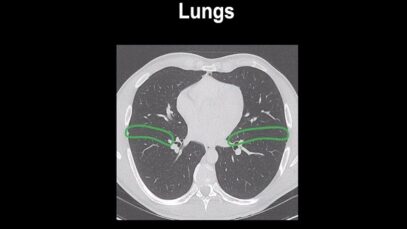

computed tomography of the chest Computed tomography (CT) is an imaging technique that has revolutionized medical imaging. It is widely available, fast, and provides a detailed view of the internal organs and structures. Helical CT is most common, but conventional, axial, step-and-shoot CT is used for thin section high-resolution CT scanning of the lungs, coronary […]